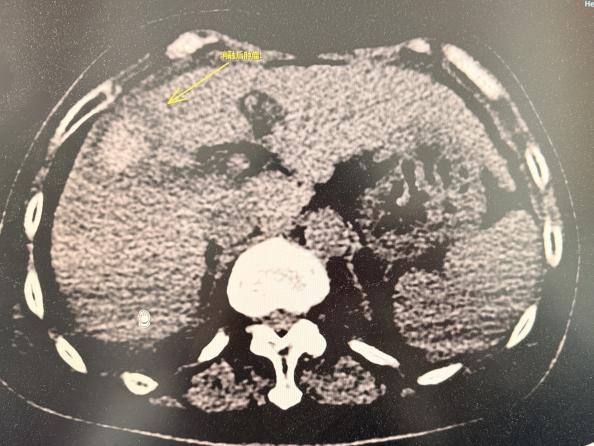

消融术前影像

术中,患者生命体征极度不稳定,血氧饱和度在70%至90%之间波动,呼吸急促导致消融针随膈肌大幅摆动,CT影像出现明显重影,为精准穿刺带来极大挑战。治疗过程中医生们沉着冷静、各司其职:麻醉科郭振海教授全程严密监护,精细调控呼吸与心率,确保能在血氧短暂回升至90%的宝贵窗口期内进针;陶冀教授团队则采取“阶梯功率、分次消融”策略,首轮以40-50-70W功率渐进消融9分钟后,调整针道进行第二循环治疗,最终完整覆盖两处紧贴肝被膜的病灶,肿瘤完全消融。历时2小时,手术顺利完成,患者未出现出血、气胸等并发症,术后生命体征逐步平稳,实现精准消融与安全治疗的双重目标。